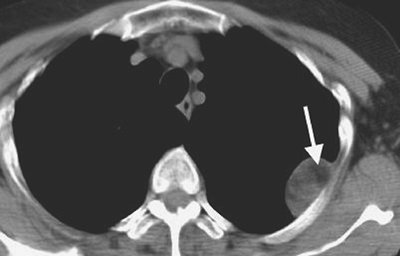

FIGURE 9-10. Hemothorax. CT shows high-attenuation blood (H) in the right pleural space.